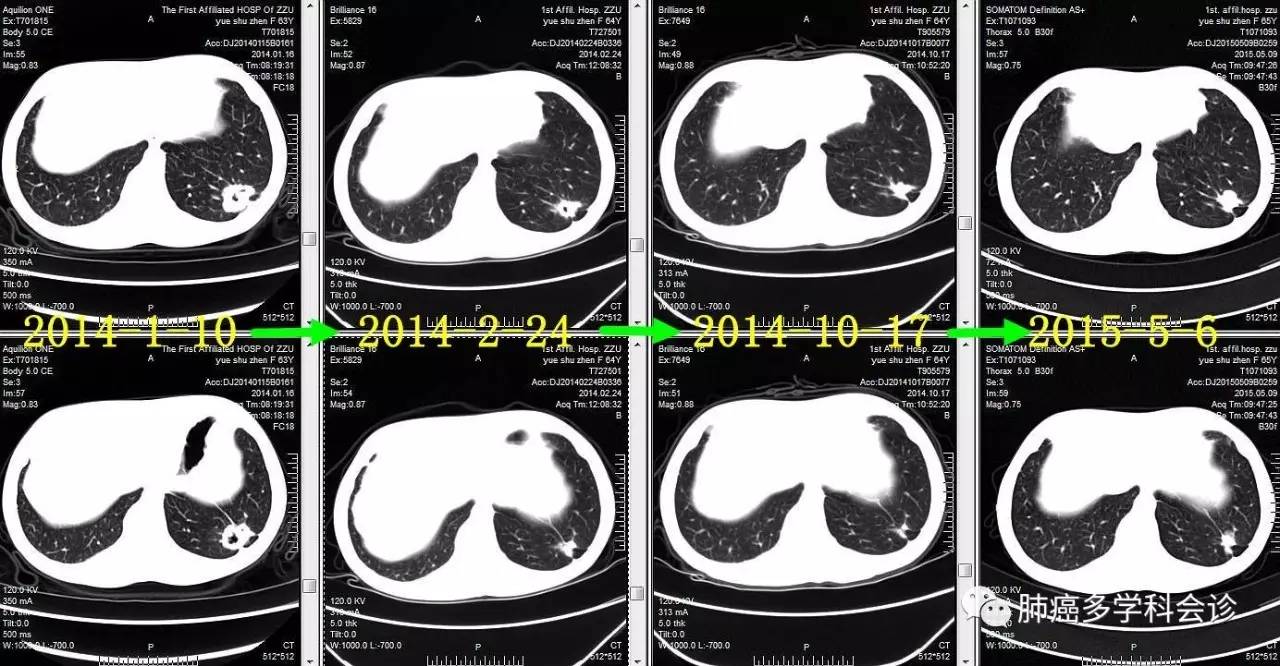

患者岳SZ,女,68岁。2014年1月,因咳嗽吐痰做CT发现左下肺占位、纵隔和双肺门淋巴结肿大;头颅MRI发现左侧额叶转移瘤。SPECT示:左侧第2前肋局部骨代谢异常活跃,结合CT考虑骨折。

●2014.01 ~ 2016.03 口服易瑞沙获部分缓解,服药共2年余后因疾病进展而停用。以下是治疗过程中胸部肿瘤CT图像的变化:

微信图片_20170523115459.jpg

●2015-5 ~ 2015-8,PEM+NDP化疗4周期,PEM单药1周期,进展。